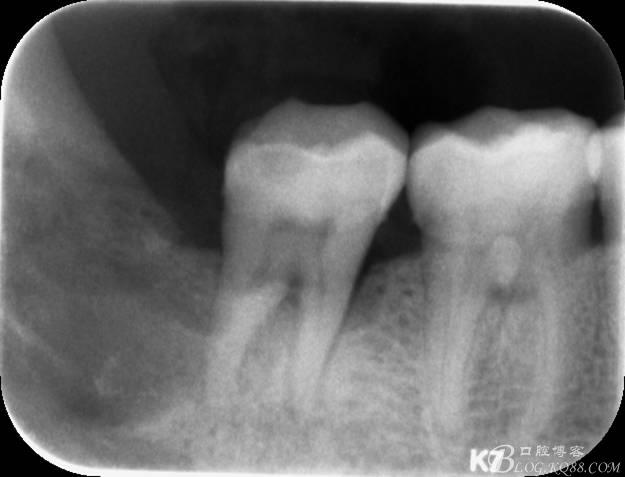

48未萌出,47遠中可探及深約7mm的牙周袋。頰側47、48之間牙齦紅腫,有少量血性滲出。X線根尖片顯示:48牙冠反轉倒置,47遠中牙槽骨吸收明顯。CBCT顯示:48牙冠近中面位于下頜管內。

一、術前全景片影像: